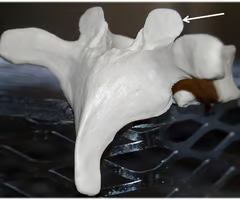

Herniated (slipped) disc

Occurs when spongy nucleus pulposus protruded thru a rupture in annulus fibrosus and presses on the spinal cord or spinal nerves.

Nucleus pulposus

Annulus fibrosus

Herniated (slipped) disc